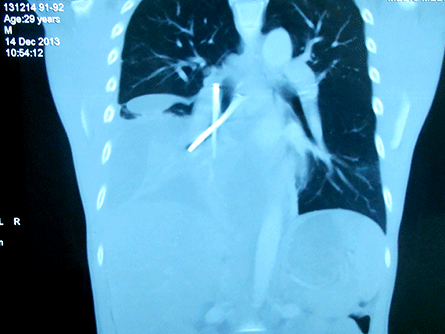

| Hai cây đinh đã được các bác sĩ mổ lấy ra khỏi bụng bệnh nhân. |

Qua các xét nghiệm máu cần thiết, chụp CT 64 lát cắt ở ngực, bụng, các bác sĩ tại BV Hoàn Mỹ Sài Gòn đã phát hiện bệnh nhân bị tràn dịch màng phổi phải lượng nhiều, tạo khoang, dị vật dạng 2 cây đinh bắt chéo chữ X trong phế quản trung gian phổi phải.